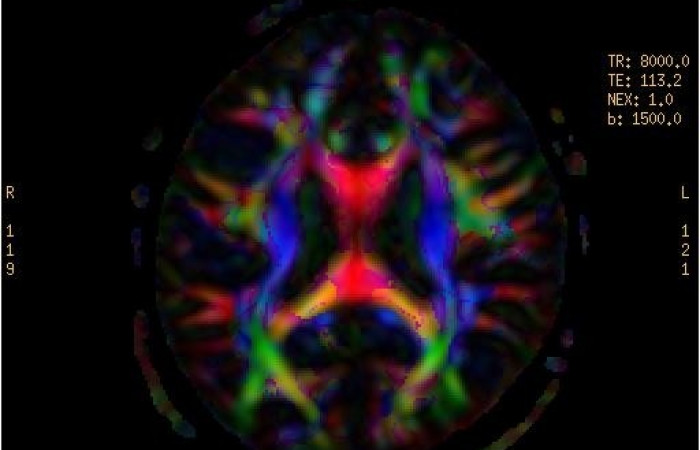

ˇ badanie dyfuzyjne mózgu z traktografią

- Dyfuzja MR z traktografią pozwalającą na prezentację dróg nerwowych

- Obrazowanie funkcjonalne